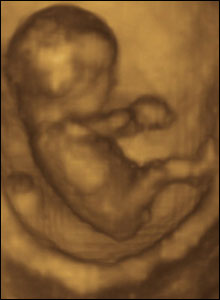

“Abortion is undeniably the taking of potential life. It is not pretty. It is not easy. And in a perfect world, it would not be necessary.”

Dr. Slepian uses the term “potential life” to soften the impact of what he is saying. However, some abortionists have come out saying that abortion takes a life without using the word “potential.”